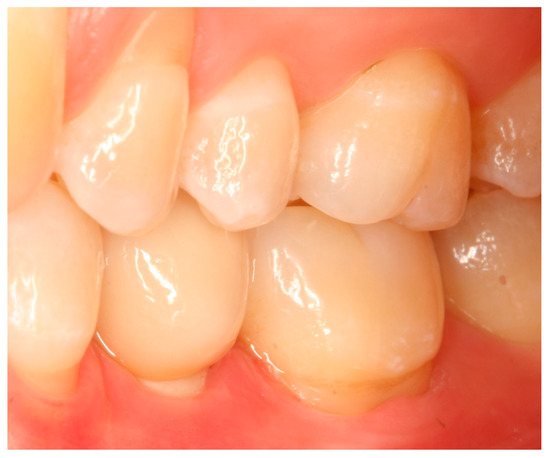

Situation after crown cementation. Lateral view.

Clinical situation at the 1-year follow-up. Lateral view.

Clinical situation at the 3-year follow-up. Lateral view.

Clinical situation at the 5-year follow-up. Lateral view.